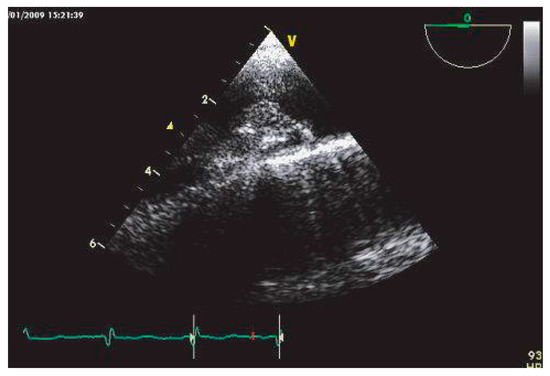

Echocardiographie et Sources Cardiaques d'embolie

• Ariel Cohen

Cardioembolic stroke is the second cause of ischemic stroke, with a high rate of morbidity and mortality. Echocardiography, mainly transesophageal echocardiography, is very useful for the diagnosis and risk stratification of the various potential car...